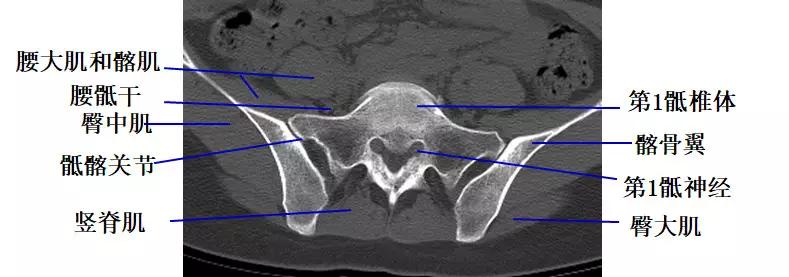

经第1骶椎椎体的横断层面(CT)